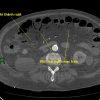

Nhồi máu ruột

» Thông tin: Nam giới – 85 tuổi.

» Lâm sàng: Đau bụng cấp.

# Dày thành ruột – Khí thành ruột – Khí tĩnh mạch mạc treo.